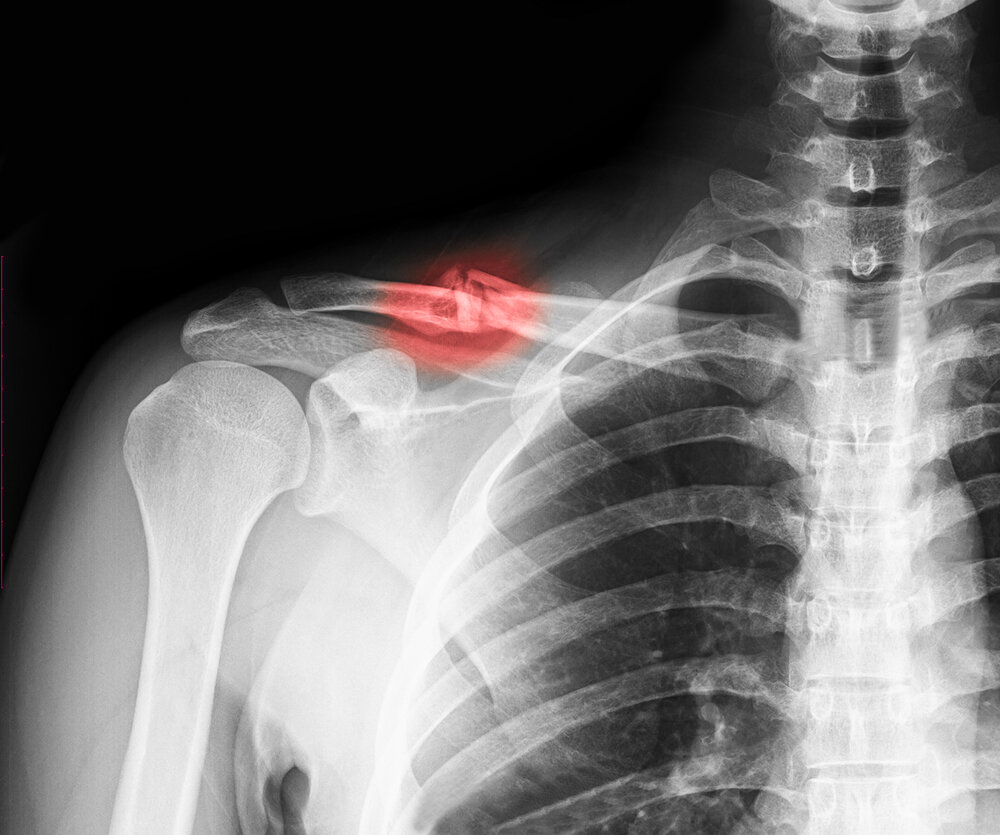

Ключичная кость – симметричная S-образная косточка, которая расположена горизонтально над грудиной. Ключица соединяет лопатку с грудной костью и укрепляет амплитуду плечевого пояса. Перелом ключичной кости чаще случатся в самой тонкой ее части и сопровождается следующими симптомами:

• визуальная деформация ключицы;

• перекос плечевой линии (с опущением поврежденного плеча);